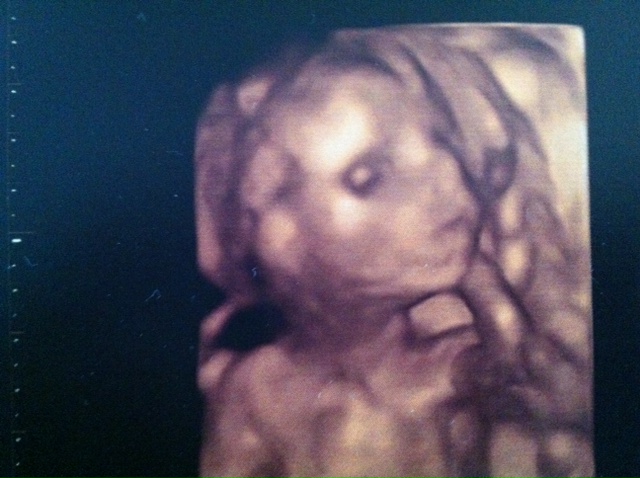

Finally decided to go and have a private scan done, they confirmed for me a little girl is on her way and we finally got a decent potty pic. Ladies you have made this waiting game a whole lot easier, thank you for everything :)

Looking forward to my little girl being a big sister :kissy: